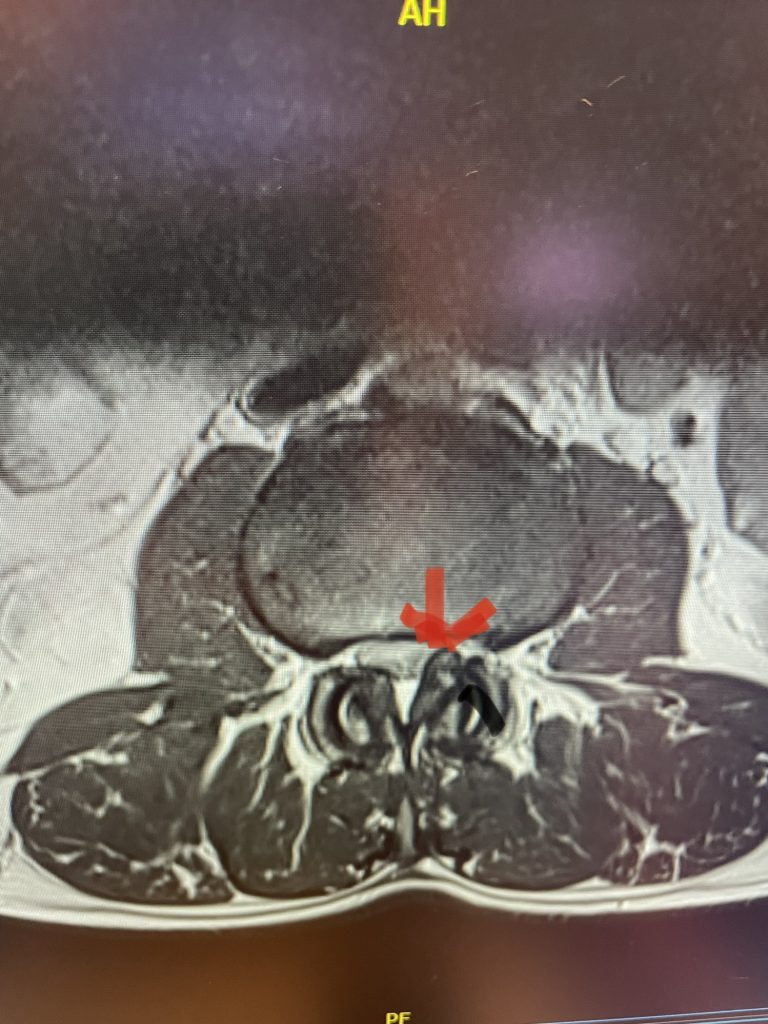

The spinal synovial cyst is one of the most interesting expressions of spinal instability. They emanate from the synovial lining of a degenerated facet joint that […]